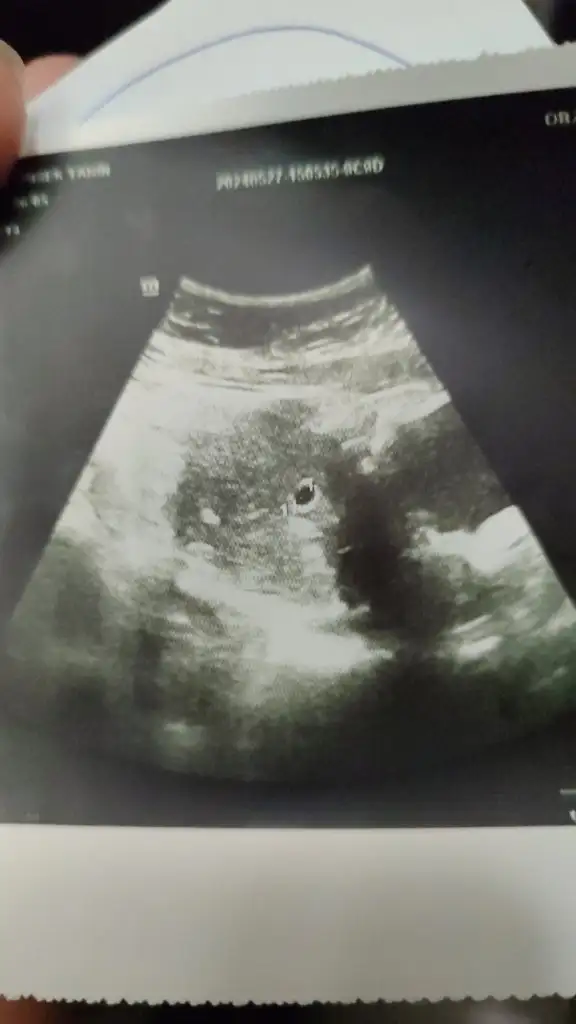

Merhaba 11hafta 4gunluk karından çekilmiş ultrason bende merak ediyorum cinsiyetini

• IMG_20240603_134244_688.webp

IMG_20240603_134244_688.webp

21,7 KB · Görüntüleme: 57